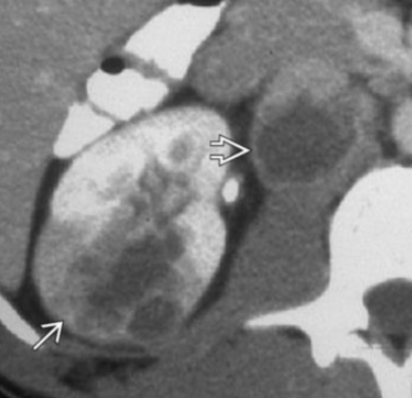

Hypertrophy of Column of Bertin

• Refers to enlarged piece of renal cortex that protrudes through the medulla

• Commonly mistaken for a renal mass

• Isoechoic/Isointense/Isodense to renal cortex

• Will show communication with the regular peripheral renal cortex

• Usually unilateral and on the left